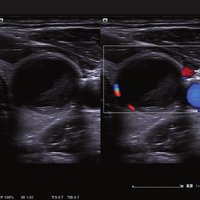

Das ACUSON NX2 Ultraschallsystem besitzt eine zukunftsfähige digitale Plattform mit nahezu unerreichter Bildqualität und sorgt für effiziente und zuverlässige Diagnosedaten. Die Vielseitigkeit des Ultraschallsystems wird mit einem großen kompatiblen Portfolio an Schallköpfen gedeckt, und so ist für jeden Anwendungsbereich etwas dabei. Die Bedienkonsole ist intuitiv aufgebaut und optimiert und erlaubt bis zu vier nach vorne gerichteten Schallkopfanschlüssen für eine enorme Effizienz und schnellen Workflow. So lassen sich bei der fetalen Bildgebung außergewöhnlich detailgetreue Darstellungen des Fetus im Gesicht zeigen oder durch die herausragende Farbdopplersensitivität bei der Darstellung der kleinen Gefäße des zystischen Schilddrüsenknotens kleinste Details erkennen. Weiterhin besticht das NX2 mit einfacher Aufrüstbarkeit bei wachsenden Anforderungen für Ihre zukünftigen Anwendungen und kompatible skalierbare Schallköpfe verringern ihren Kapitaleinsatz um bis zu 31 %.

• Oberflächennahe Organe (Small Parts)